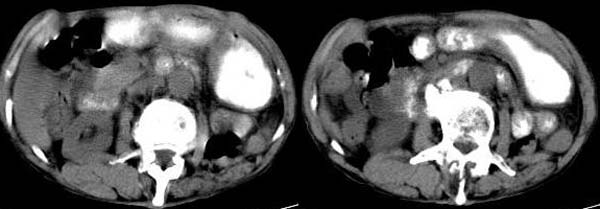

男 74岁,聋哑人,病史不详。

升结肠壁不均匀增厚,周围境界尚清,腹主动脉旁、盆腔内未见肿大淋巴结,考虑:升结肠癌可能性大.

升结肠壁明显不规则增厚,呈偏心性,考虑结肠癌。

充盈欠佳,结肠肝曲壁不规则增厚,考虑结肠ca,建议取材!

升结肠壁不均匀增厚,肠腔偏心性狭窄,周围境界尚清,腹主动脉旁、盆腔内未见肿大淋巴结,考虑:升结肠癌可能性大.建议:纤维结肠镜检查.

升结肠壁明显不规则增厚,呈偏心性,考虑结肠占位性病变建议行钡剂灌肠